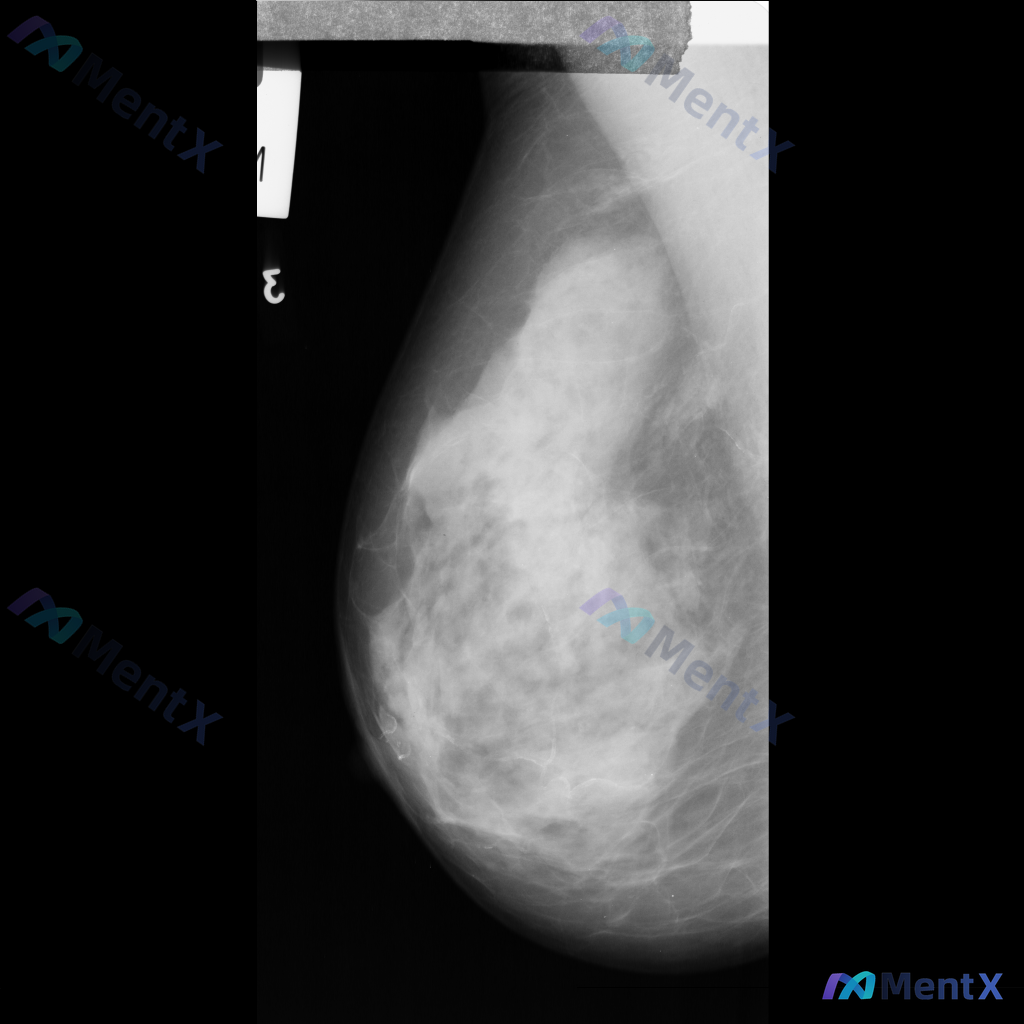

整理到一份单侧乳腺钼靶MLO位的影像资料,想和大家讨论一下初步判断思路。 影像基本情况 - 投照位置:单侧乳腺MLO位 - 主要表现:乳腺组织不均匀致密,ACR BI-RADS c类;在致密的腺体背景下,可见部分区域的致密影,但边界比较模糊,暂不能明确界定为独立肿块。 目前只有这一个位置的影像资料,...

整理到一份乳腺钼靶的影像讨论资料,背景是不均匀致密型乳腺(BI-RADS C类),主要发现是一处不对称致密影——目前描述里没有提到明确的肿块、簇状微钙化或结构扭曲这类典型征象。 想跟大家讨论一下: 1. 单看这组表现,你第一反应会先往哪个方向考虑? 2. 这种情况下,你觉得最需要优先补充的评估是什么...